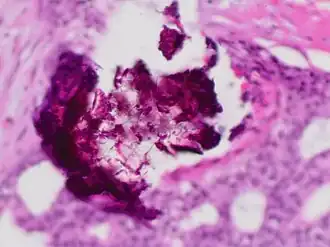

Calcium phosphate is the usual constitution of microcalcifications of the breast, particularly dystrophic calcifications. Microcalcifications as can be seen on mammography can be an early sign of breast cancer. Based on morphology, it is possible to classify by radiography how likely microcalcifications are to indicate cancer.[8]

Histopathology of dystrophic calcium phosphate microcalcifications in ductal carcinoma in situ (DCIS) of the breast, H&E stain.